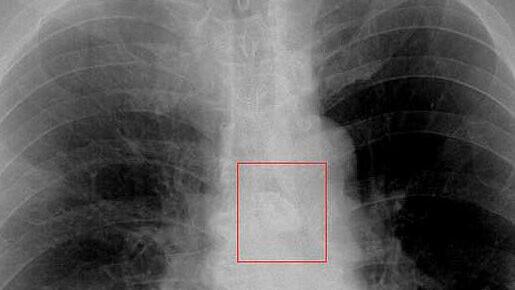

Zwei Ein-Cent-Stücke, rechts im zersetzten Zustand, liegen nebeneinander. In der Lunge eines Patienten mit monatelangem hartnäckigen Husten hatten Ärzte das zersetzte Geldstück gefunden.

Doch wie konnte es überhaupt zu diesem Vorfall kommen? Der Patient erinnerte sich daran, wie er im Januar beim Dart-Spielen eine Ein-Cent-Münze verschluckte. "Mein Kumpel hat mir auf den Rücken geklopft, ich habe mich kurz erschrocken und die Münze, mit der ich am Mund gespielt habe, verschluckt. Was rein geht, findet den Weg auch wieder raus, dachte ich und habe mir weiter keine Gedanken gemacht", zitierte die Klinik den Patienten in der Mitteilung. Ein heftiger und hartnäckiger Husten trieb ihn dann doch zum Arzt. Auf dem Röntgenbild konnten die Ärzte im Bronchialsystem der Lunge einen wahrscheinlich metallenen Fremdkörper erkennen - und beschlossen schnell zu handeln.